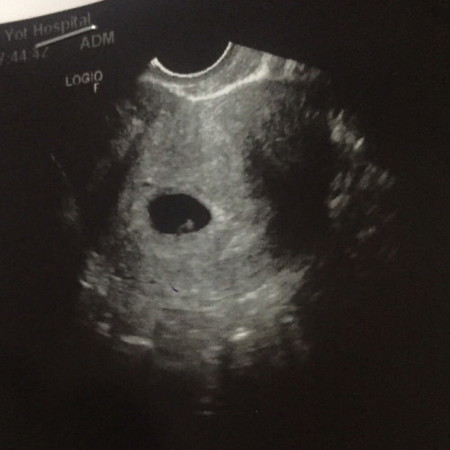

ช่วยดูหน่อยแม่ๆ เป็นถุงไข่ หรือ เจ้าตัวน้อย 6w3d

ก้อนจิ๋วๆนั้น จะเป็นตัวอ่อน หรือ รังไข่ คะ แม่ๆ ช่วยดูหน่อย ไปตรวจ รพ รัฐ หมอพูด วกๆวนๆ พอเราถามซ้ำ ยิ่งฟังยิ่ง งง😂 6w3d หมอนัดอีกที 24 มค นี้ อยากได้ยินเสียงตุ๊บตั๊บๆของตัวน้อยจัง ( แม่เสี่ยงความดันอีกทำไงดี อยู่บ้านความดันปกติ พอไป รพ ความดันขึ้น หมอจะลงความเห็นว่าจะเป็นความดัน😢)

น่าจะตัวอ่อนน้องค่ะ ยินดีด้วยนะคะคุณแม่ บ้านนี้รู้ว่าท้องไปตรวจตอนเจ็ดวีคเจอตัวอ่อนแล้วก็ได้ยินเสียงหัวใจน้องแล้วค่ะ

มีถุงไข่แดงแล้วคุณแม่ ไม่ท้องลมค่าา ยินดีด้วยนะคะ ไม่ต้องกังวัลน้าแม่

ตัวอ่อนกับถุงอาหารน้องค่ะแม่ ที่วงๆอยู่นั้นคือถุงไข่แดงของน้องค่ะ